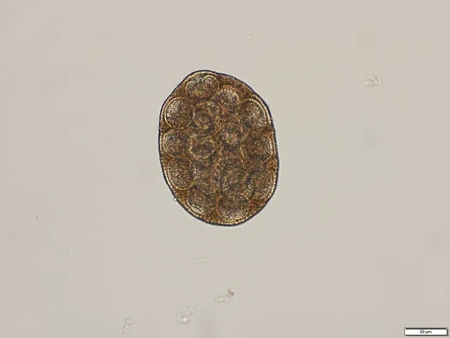

Les protozoaires et cestodes

Nommez les protozoaires et les cestodes illustrés.

Protozoaire

Cestode